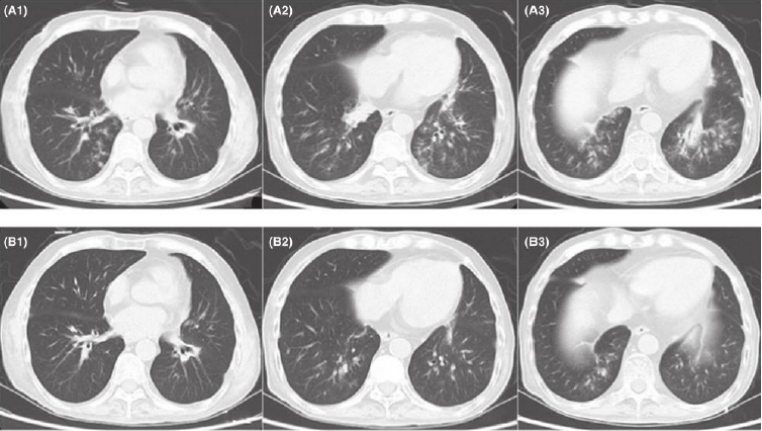

2021年1月11日(术后约2周)回报BALF GM试验6.38(↑),血GM试验阴性;BALF真菌涂片及培养均阴性;BALF CMV核酸检测阳性(CT值26.2);BALF细菌培养提示碳青霉烯敏感的铜绿假单胞菌。胸片如图11所示,气管镜下可见黏膜充血明显。

图片

11  患者肺移植术后第12天胸片及气管镜下所见

虽然此时没有BALF真菌培养阳性结果,但BALF GM试验显著升高,且该患者属于侵袭性真菌病IFD高危人群单肺移植CMV核酸阳性,淋巴细胞绝对值减低,早期使用广谱抗生素12因此给予IFD抢先治疗,调整抗真菌方案停卡泊芬净,调整为伏立康唑200 mg q12h起始(首剂400 mg)同时进行伏立康唑血药浓度监测13继续哌拉西林他唑巴坦静点+阿米卡星雾化铜绿假单胞菌治疗。